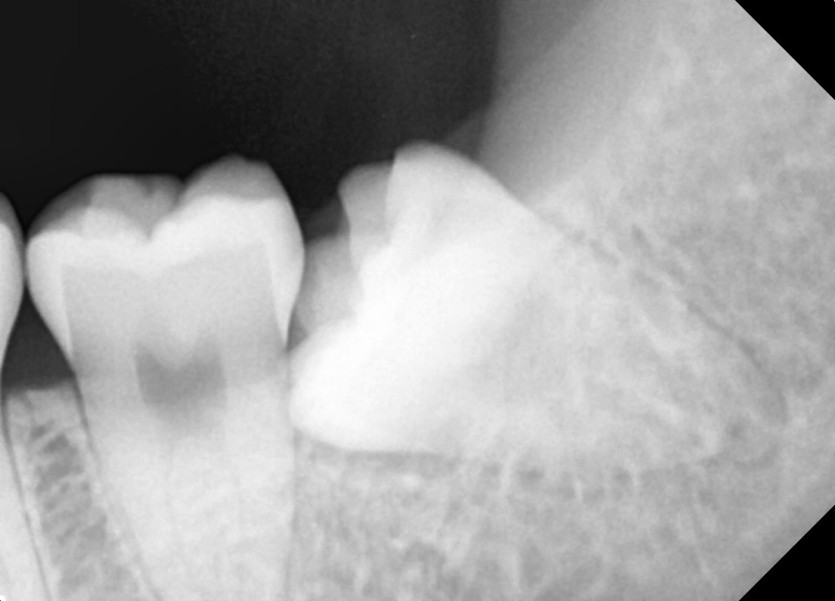

#18,28,38,48 사랑니 발치

구강 외과 전문의가 당일 발치했습니다.